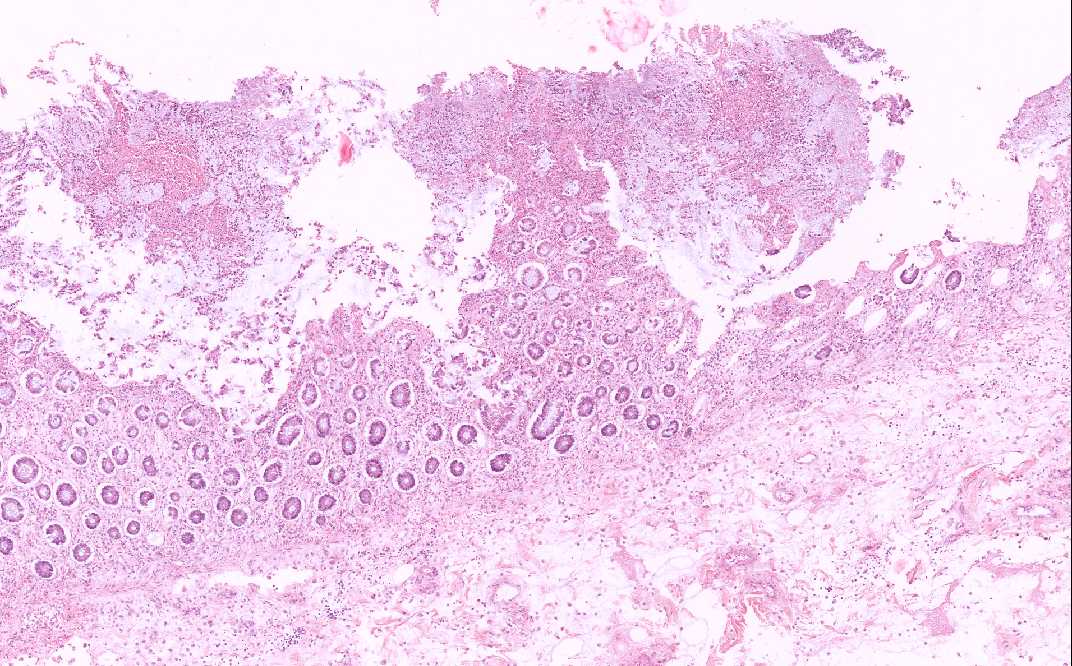

• The submucosa (S) is rather edematous and the organization appears loose. The mucosa is rather irregular and is coated by a layer of inflammatory and necrotic substance. There is also patchy necrosis of the superficial aspect os of the mucosa. In the smaller lesions, the affected crypts become dilated and exude an inflammatory and necrotic substance reminiscent of a erupting volcano or mushroom-like structure (Area 1). There is extensive loss of colonic glands due to the necrosis. In the more severely affected areas, the inflammatory and necrotic substance  fuses together to form a pseudomembrane (Area 2). This pseudomembrane extends laterally to overlie adjacent normal appearing mucosa. The exudate is composed largely of karyorrhectic debris and neutrophils. Also the mucin has a tendency to alig with the necrotic debris and neutrophils in an interesting linear arrangement (Area 3).